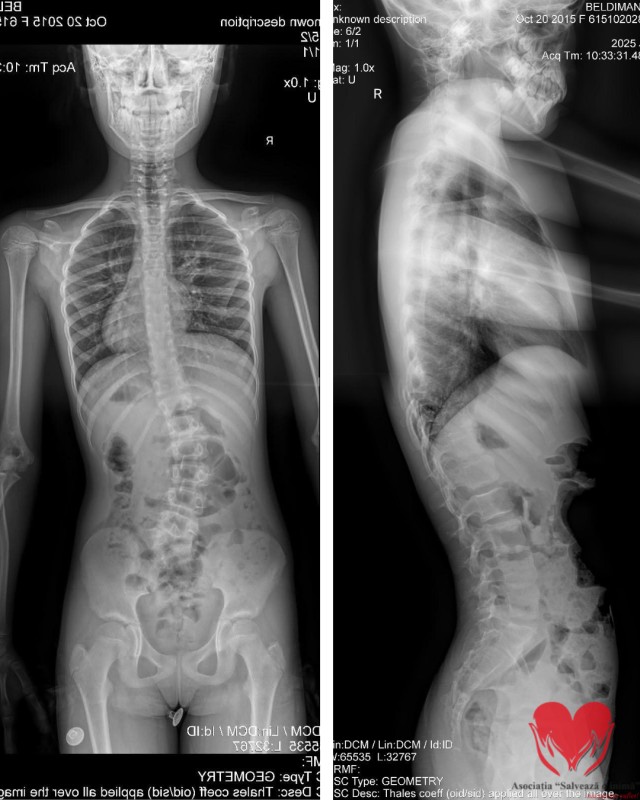

Eva Maria Raluca Beldiman are 10 ani. În scrisoarea medicală scrie simplu, vârsta și diagnosticul: hemivertebră lombo-sacrată L5 stânga complet segmentată. În realitate, povestea ei înseamnă mult mai mult decât un cod medical.

Totul a fost descoperit întâmplător, la 5 ani, în urma unei radiografii. Medicii căutau un bănuț înghițit accidental. Au găsit însă altceva: o coloană care nu creștea drept. În timp, investigațiile au confirmat scolioza toraco-lombară, iar cauza a devenit clară – o vertebră formată incomplet, care împinge coloana să se deformeze progresiv.

În interior, însă, fiecare lună înseamnă o curbură care poate avansa. Fără intervenție chirurgicală – hemivertebrectomie prin tehnica Ruf-Harms – deformarea va continua. Cu intervenția, există șansa unei dezvoltări normale.